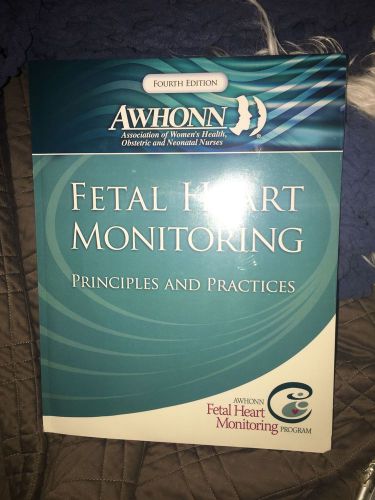

AWHONN 4th Edition Fetal Heart Rate Monitoring